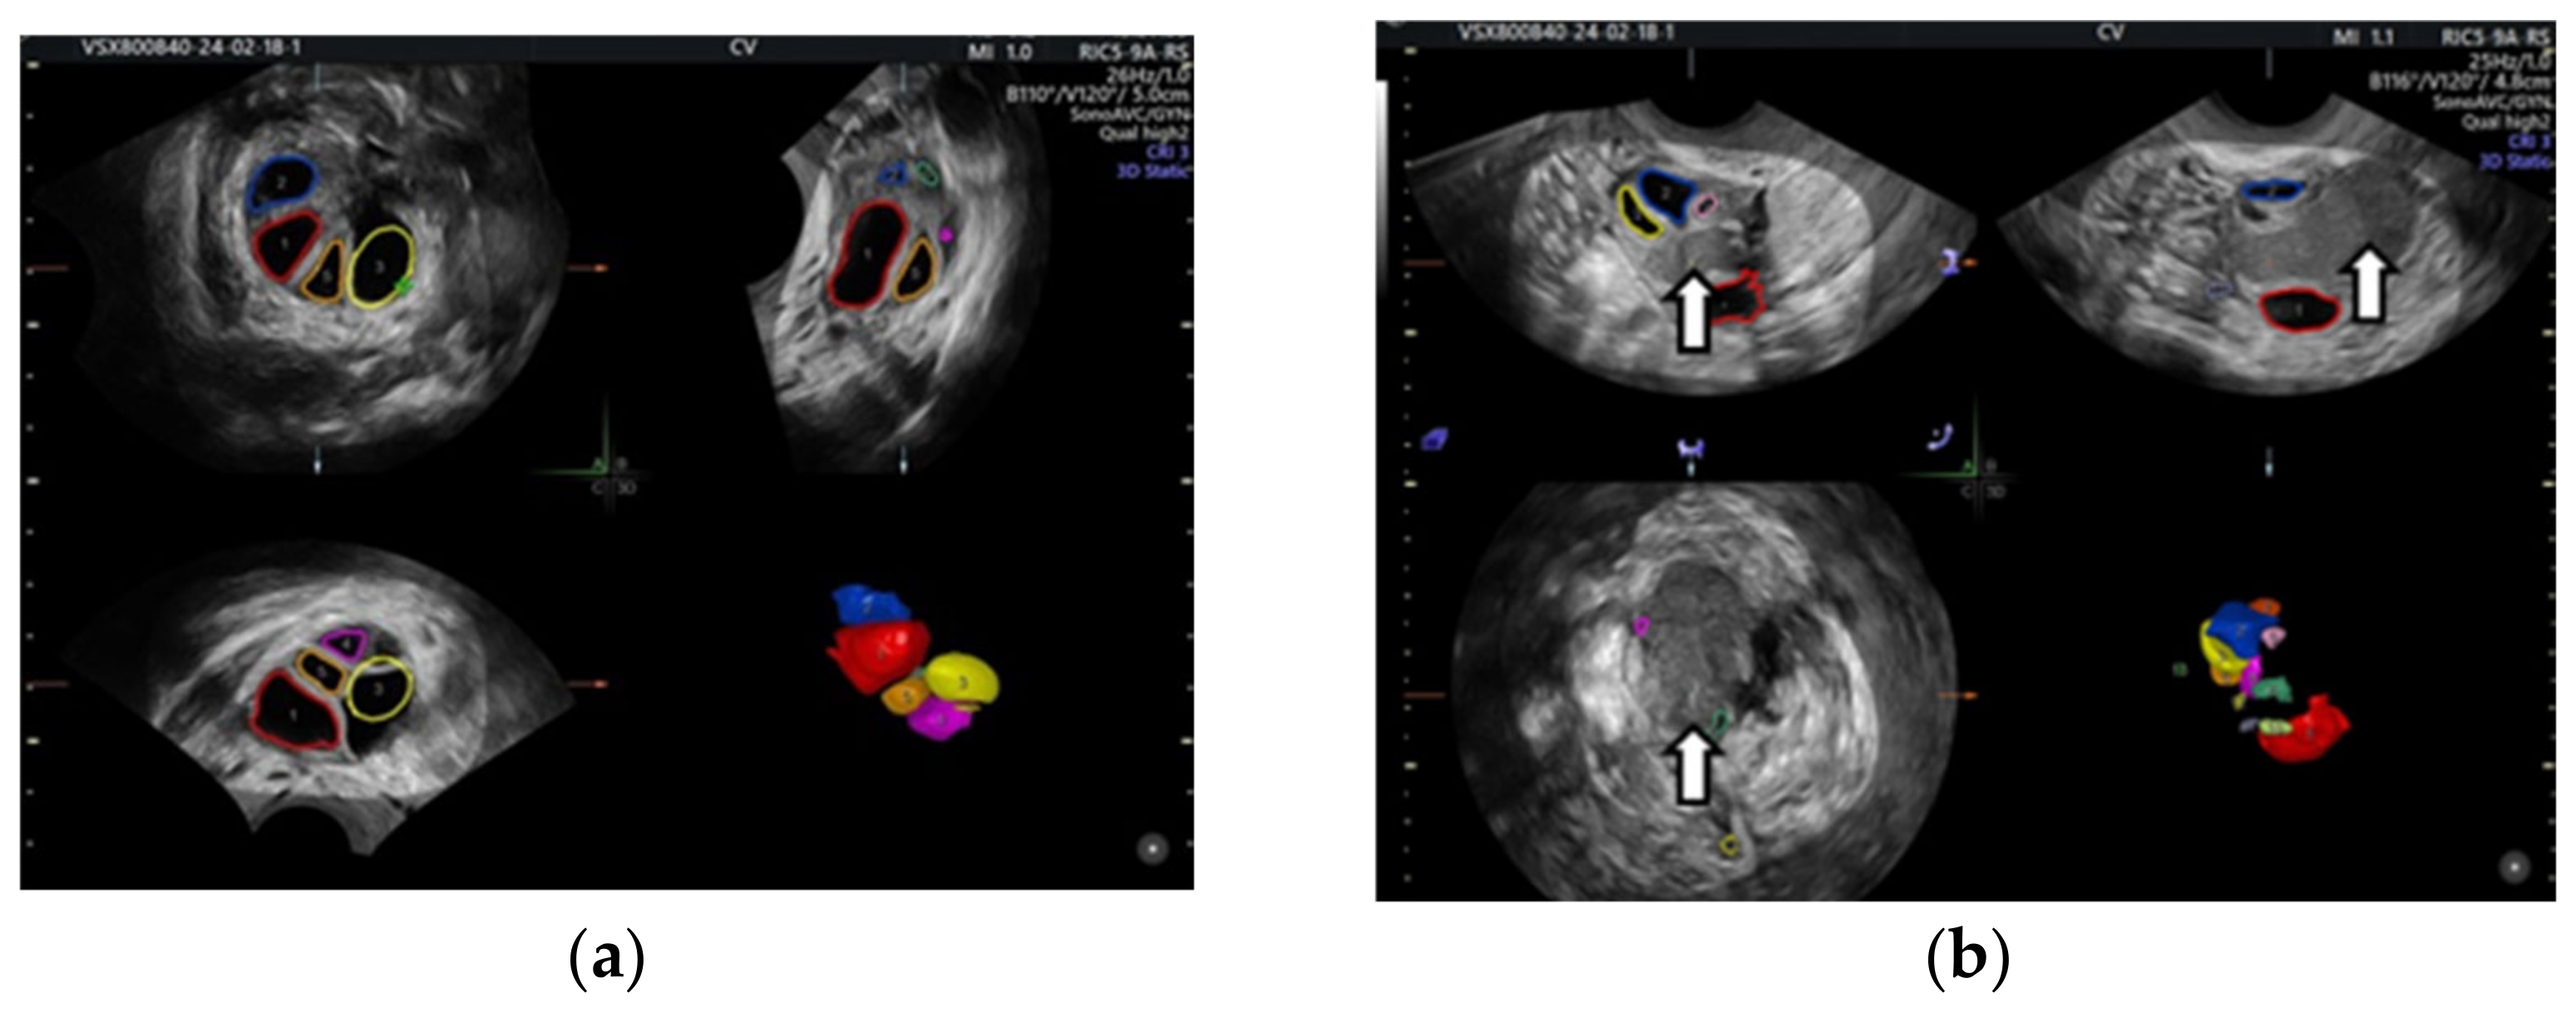

6.1.3. Imaging